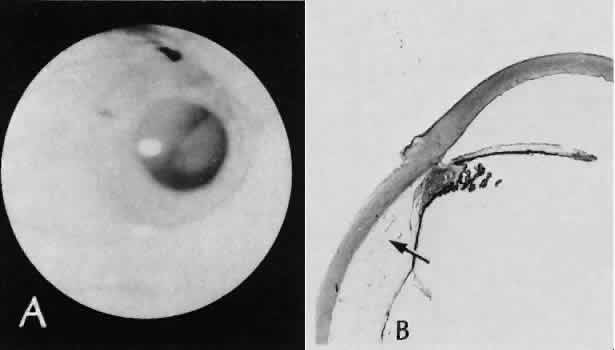

Fig. 32. A case of retinal detachment. A. In this case, the iris has become incarcerated into a limbal wound. A series of events leads to total retinal detachment (morning glory detachment). The presence of multiple areas of macrocystic degeneration of the detached retina indicates that the situation is chronic and probably not repairable. B. The histologic section of this case indicates the extent of iris incarceration and the fragility of the wound. (Hematoxylin-eosin stain; × 40.)

Fig. 33. A case of iris prolapse through a limbal wound. A. A large black mass has appeared at the limbus of a patient with a history of cataract extraction. There may or may not be a history of trauma or Valsalva maneuver. The differential diagnosis at first glance would certainly include primary conjunctival malignant melanoma or extraocular extension of a primary uveal malignant melanoma. A major differential observation from iris prolapse is the character and degree of alteration of the iris tissue remaining within the eye. B. By histologic section no cellular mass is present either in the episcleral or uveal tissue. The remaining iris is stretched and adherent to the posterior corneal surface. (Hematoxylin-eosin stain; × 40.)